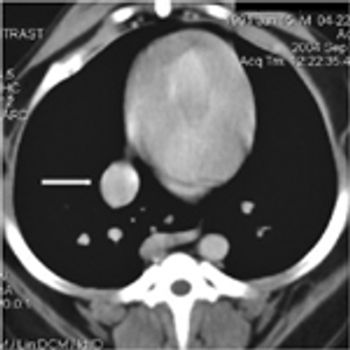

A 13-year-old 35.2-lb (16-kg) neutered male bichon frise was referred to the Veterinary Emergency Clinic in Toronto, Ontario, for evaluation of a caudal thoracic mass that had been identified radiographically by the referring veterinarian.